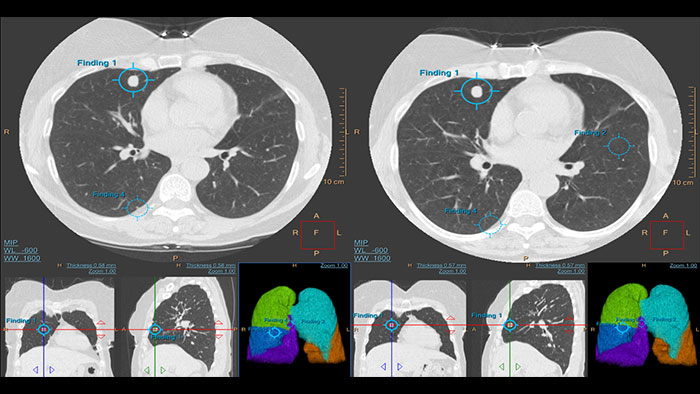

CT Lung Nodule Assessment (LNA)

Assessing lung nodules over time

Enables review and analysis of thoracic CT images, providing segmentation, quantification and characterization of physician-indicated lung nodules. The application can be used in both diagnostic and screening evaluations, supporting Low Dose CT Lung Cancer Screening*

Benefits

- Automatic lung and lobes segmentation and one click 2D and 3D nodule segmentation.

- Supports LungRADS categorization, Fleischner Society guidelines for incidental findings as well as a Risk Calculator tool**.

- Pre-filled data including characteristics for each nodule in configurable presets are provided automatically by the application.

- Lung and nodule segmentations can be shared as RT Structures.